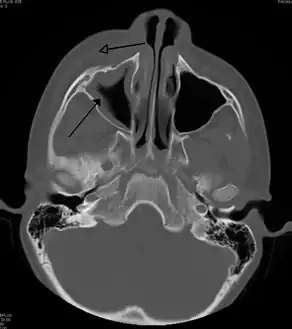

A CT scan showing sinusitis of the ethmoid sinus | |

For sinusitis lasting more than 12 weeks, a CT scan is recommended.[54] On a CT scan, acute sinus secretions have a radiodensity of 10 to 25 Hounsfield units (HU), but in a more chronic state they become more viscous, with a radiodensity of 30 to 60 HU.[56]